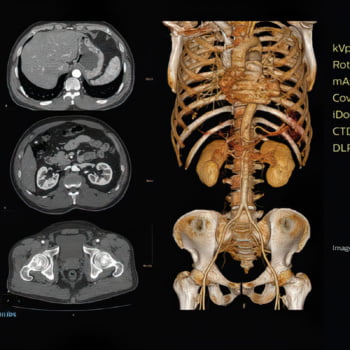

IDose é uma tecnologia Philips CT comprovada e premiada, que permite que nossos equipamentos sejam capazes de oferecer uma excelente qualidade de imagem utilizando baixas doses, prevenindo a formação de artefatos e aumentando a resolução espacial.

Veja mais detalhes em uma grande variedade de pacientes

A exclusiva tecnologia MAR reduz os efeitos de objetos metálicos na formação das imagens, permitindo a visualização da anatomia circundante. Nossa alta resolução espacial revela detalhes sutis para um alto nível de análise quantitativa, maximizando a detectabilidade de pequenos objetos.